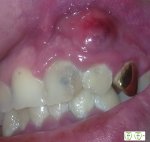

>>67737588

А мне прооперировали свищ недавно. Не дорого. Просто фоточку решила прикрепить. Повыебываться. Сейчас там тонюсенькая полоска после операционного шрама.

>>67740138

Вот тебе подробнее. К счастью у меня был совсем маленький. Мне частник сделал зуб, вроде хорошо сделал, а он болел иногда. Везде полоскать советовали. Потом вылез маленький прыщик над ним(прыщей во рту не бывает) и то надувался то вздувался, тоже советовали полоскать. Карочи загнил или типо того. Это сложная операция мне ее в самой лучшей клинике Киева делали. А в "бесплатной" предлагали нахуй удалить.